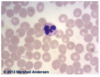

Lymphocyte 1000x